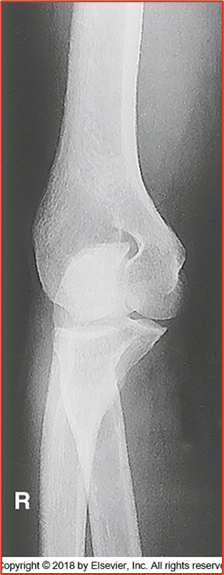

lateral oblique

this image is what projection of the elbow

which coyle method projection compromises for a lateral oblique

-Radius and ulna should be completely separated (almost there but not fully)

-There is crowning of the radial head (should NOT be present, should be flat) meaning they are not fully extended

-Capitulum and radial head present

-REPEAT because of crowning

critique this lateral oblique elbow image